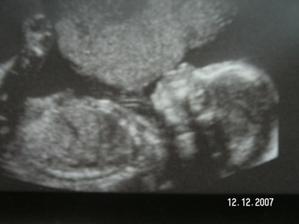

Tak jsme zpět z poradny.Jestli to bude kluk nebo holčička nevíme,protože miminko překřížilo nožky a nechtělo se ukázat.Za to na mamku krásně mávalo,tak to pan doktor zvěčnil-fotka je v albíčku.Měříme už 11cm!!!Zítra - 14.11. jdeme na tripple testy a taky na kontrolu,mamce totiž začalo nějak tvrdnout bříško,tak to pan doktor raději zkontroluje.Snad je všechno v pořádku.///Tak dneska 14.10.-na kontrole všechno v pořádku,jen placenta je trochu moc dole,ale to by se mělo do dvou měsíců upravit,mimi je o pět dní menší,ale krásné.(viz. foto).Dostali jsme magnézko na to tvrdnutí.Nabrali mi krev na tripple testy,tak se bojím,aby to bylo v pořádku.///Tak na testech jsme měli nakonec něco mírně zvýšené,ale celkem ještě v normě,tak doufám,že 12.12. na velkém genetickém UZ bude všechno v pořádku.A třeba se už konečně dozvíme,co to vlastně čekáme.///Tak jsme byli na genet.UZ-všechno je naprosto v pořádku!!!Mimi váží 360g a měří 25cm.Jsme 20+5tt.A víme,co to bude!Holčička!!!///Narazila jsem na úžasný kočárek,byla jsem z něho tak unešená,že jsme ho malé Fazolce museli pořídit.///7.1.-KO v poradně.Princezna má už 633g!!Všechno je v pořádku.Příští týden na cukrovkový test-FUJ!Můj váhový přírustek zatím 4,5kg-24+6tt.///Včera-4.2. kontrola v poradně.Všechno v pořádku.Vážíme 1255g a měříme přes 30cm.Můj váhový přírůstek - 29.tt.-asi 5,5 kg.///3.3.2008-velký UTZ,všechno v pořádku,akorát mám špatný krevní obraz,takže budeme zobat železo.Můj váhový přírůstek 7kg-33.tt.////